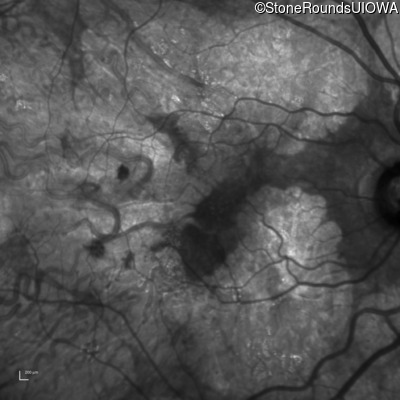

AR Stargardt Disease (IIA)

Age at visit: 51 years

This 51 year old woman first experienced some abnormality in her distance vision when she was 27 years old. She feels that her vision has been stable since that time.

Diagnosis & molecular findings

Disease Gene Allele 1 variant(s) Allele 2 variant(s) Inheritance mode

AR Stargardt Disease ABCA4 Gly1507Arg GGG>AGG IVS42+1 G>A AR